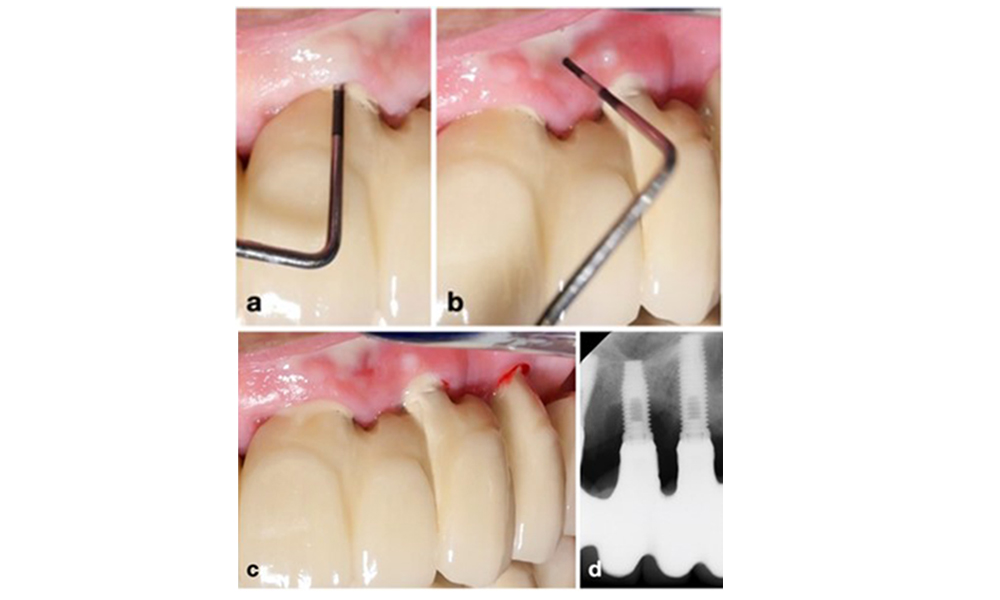

Implantat an Position 26 mit periimplantärer Mukositis (a-c). Die Sondierungstiefe von 5 mm (b) stimmt mit der wenige Wochen nach dem Einsetzen der prothetischen Rekonstruktion vorgenommenen Messung überein. Es kommt zwar zu einer Sondierungsblutung (c), aber die Röntgenaufnahme zeigt keinen weiteren Knochenverlust über das Maß hinaus, das bei einer marginalen Knochen-Remodellierung zu erwarten ist (d).

Abb. 1. Implantat an Position 26 mit periimplantärer Mukositis (a-c). Die Sondierungstiefe von 5 mm (b) stimmt mit der wenige Wochen nach dem Einsetzen der prothetischen Rekonstruktion vorgenommenen Messung überein. Es kommt zwar zu einer Sondierungsblutung (c), aber die Röntgenaufnahme zeigt keinen weiteren Knochenverlust über das Maß hinaus, das bei einer marginalen Knochen-Remodellierung zu erwarten ist (d).